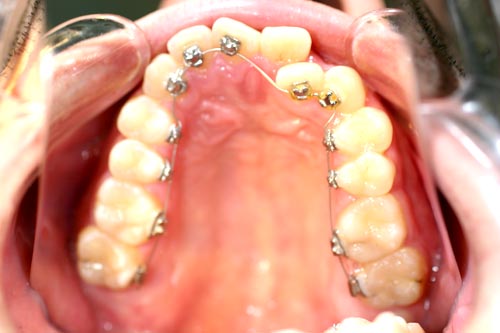

舌側矯正の治療症例

Before

After

上顎前突(出っ歯)を見えない舌側ブラケットによる矯正法で4番の歯を4本抜歯して治した症例

年齢 20代

治療期間 2年6ヶ月

治療費用 1,300,000円

治療のリスク 特になし